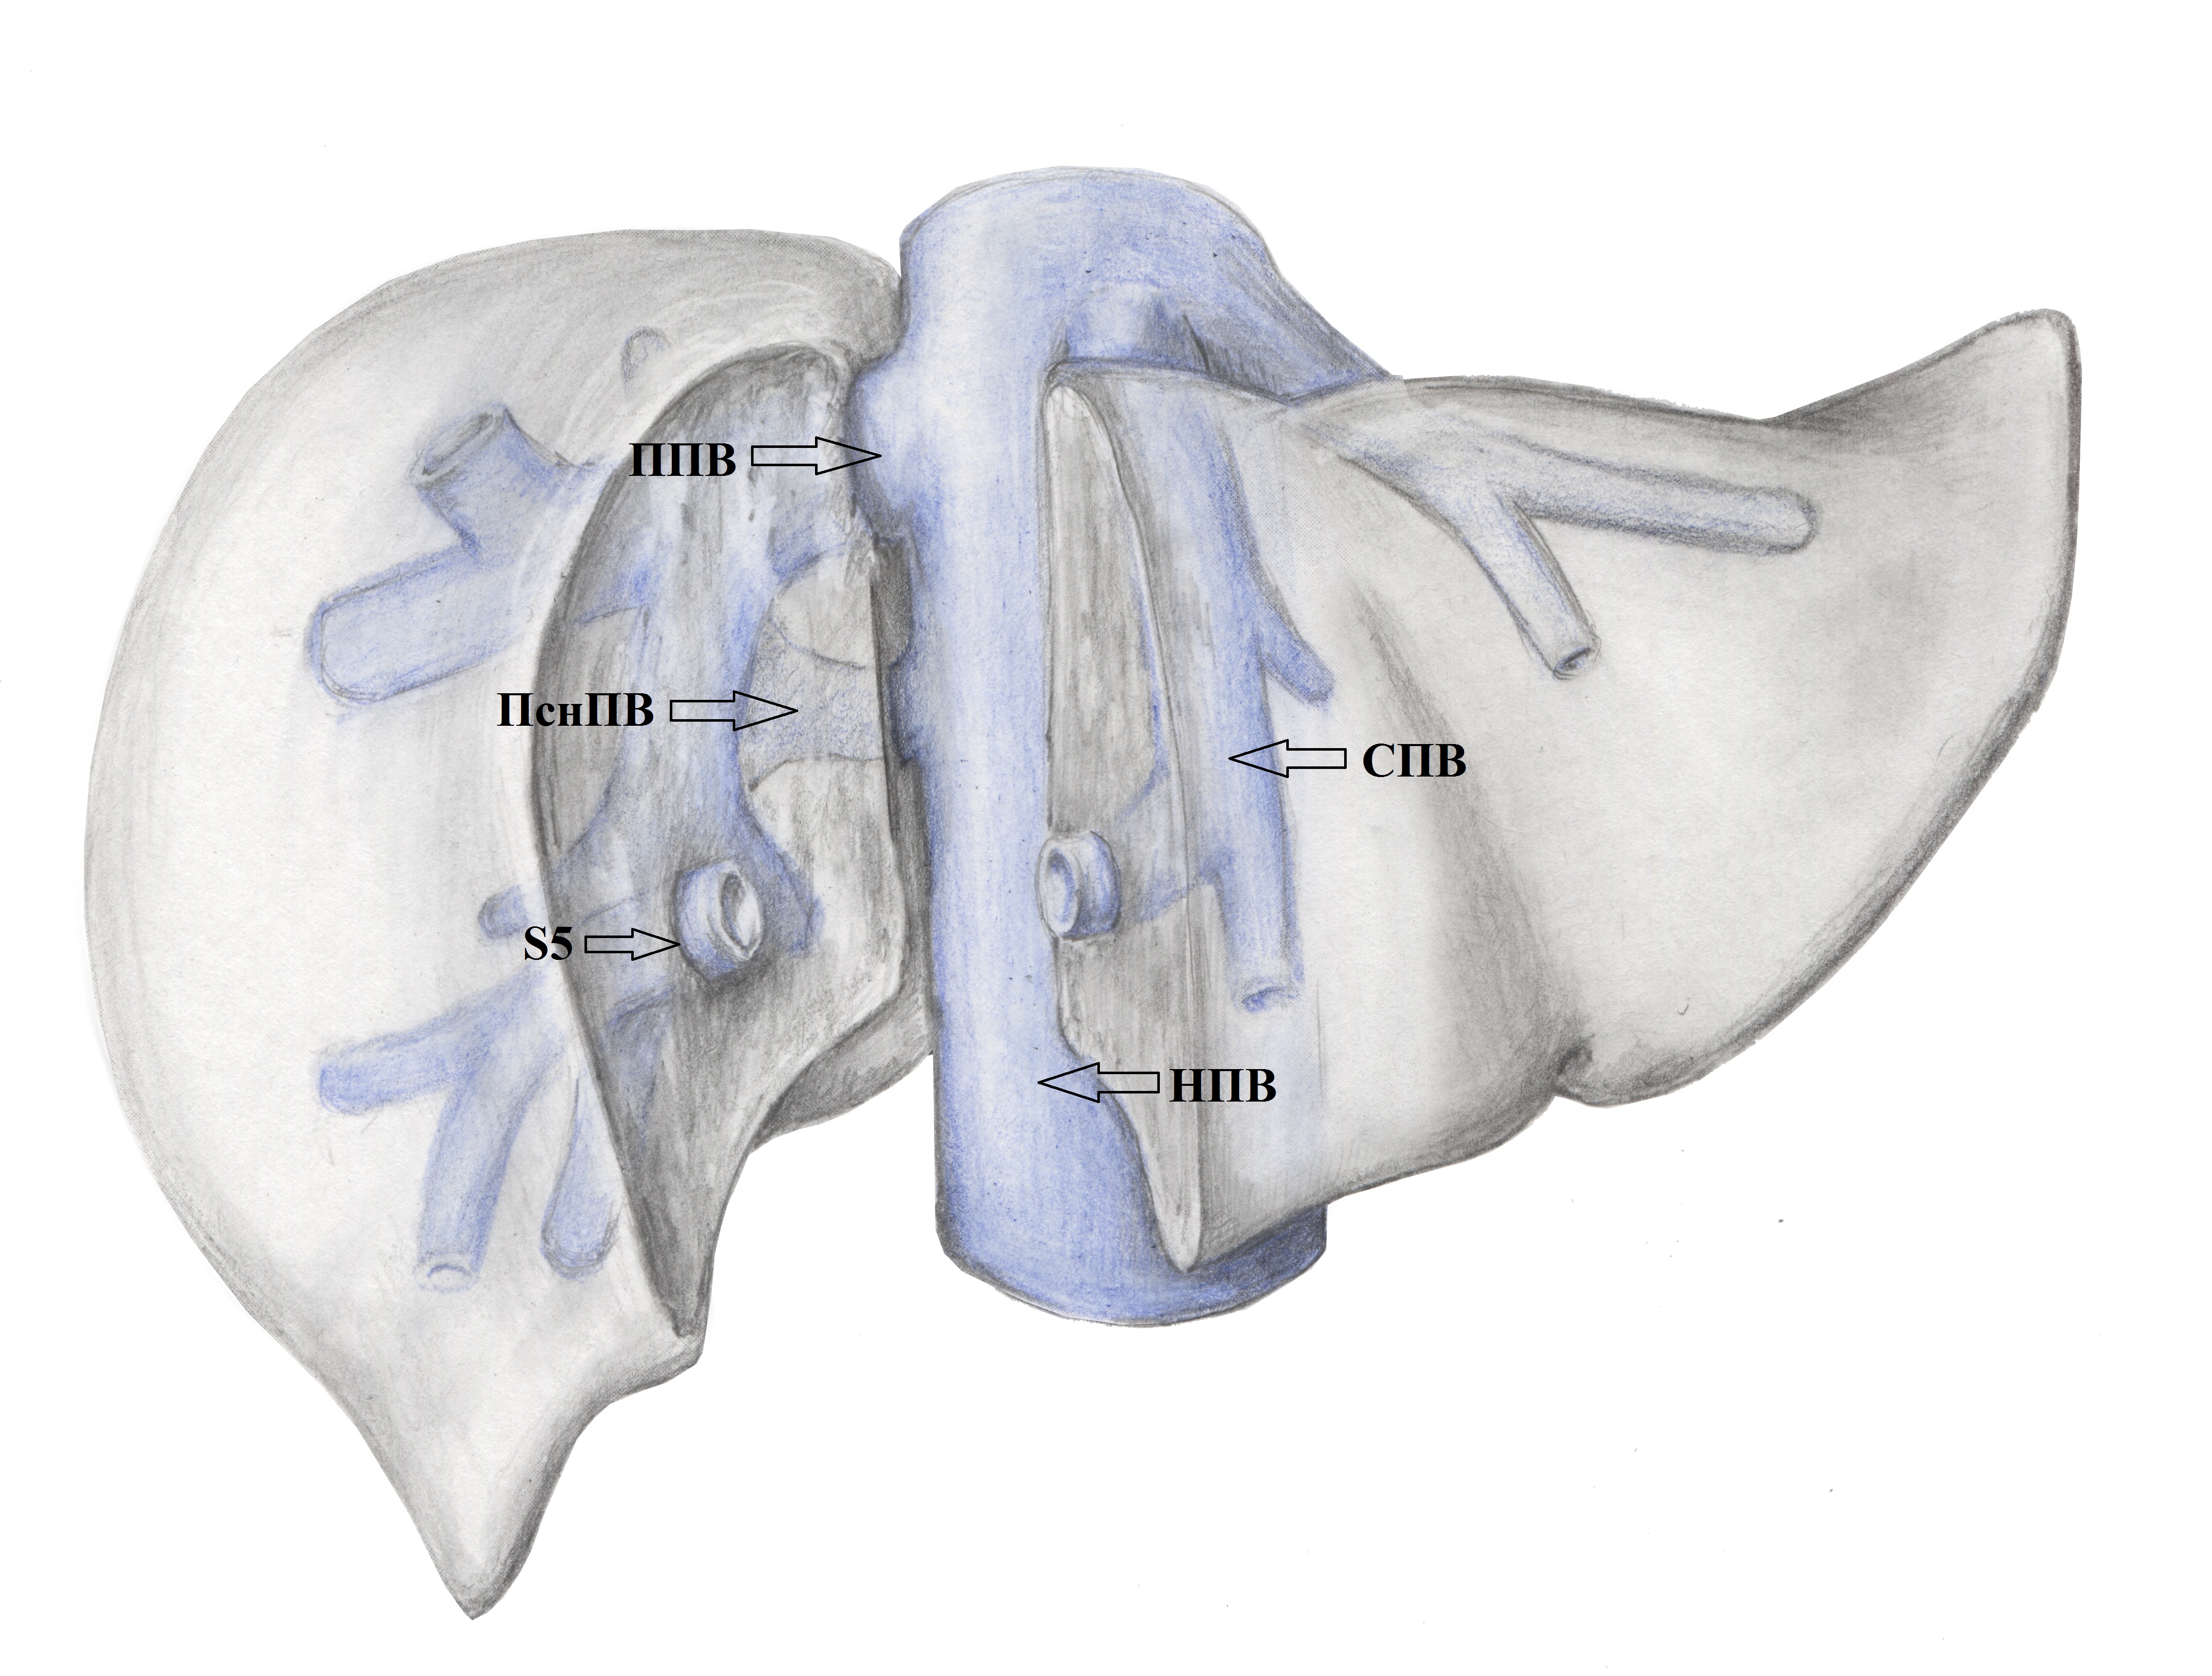

2. Тип А (схема). | |

| Тема | ||

| Тип | Исследовательские инструменты | |

Посмотреть

(1MB)

|

Метаданные ▾ | |